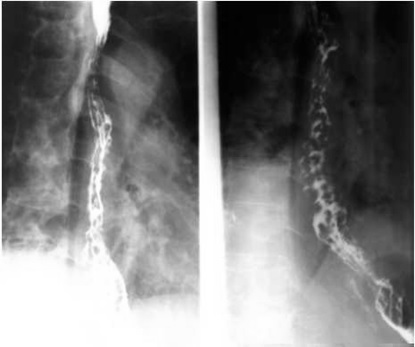

05卷-5.男性,胸骨后隐痛一年,请选择正确答案(本题满分2.00分)

造影

A.食管癌

B.食道静脉曲张

C.食道贲门失迟缓综合征

D.食管憩室

本题答案:B

题目解析:【该题针对“造影-食管静脉曲张”知识点进行考核】